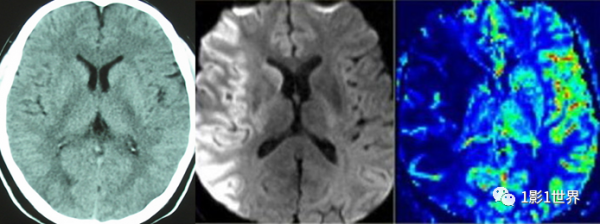

再比如,急性腦梗死,在急性期一般頭部CT會表現“正常”,報告未見異常,但是一些特殊檢查如磁共振彌散加權(DWI)序列上、在CT大腦灌注掃描上,還是會有明確的異常表現。

男,55歲,突然發現左側肢體活動不靈3個小時,頭部CT未見異常,磁共振DWI和ASL均發現右側大腦中動脈供血區異常訊號